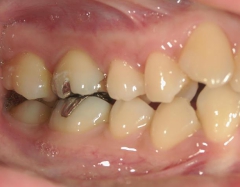

矯正歯科 治療前